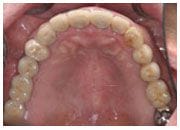

治療後

吳老師因為糖尿病所以很早就患有牙周病,早年因為植牙尚未普及,所以一直配戴活動假牙,也因為糖尿病的緣故,遲遲不敢接受植牙治療前來本診所求診時,黃醫師強調" 糖尿病患者一樣可以享受植牙的好處"現在的吳老師已經可以丟掉不舒服,吃東西又不夠力的活動假牙,使用強而有力的植牙來好好享受退休的生活。